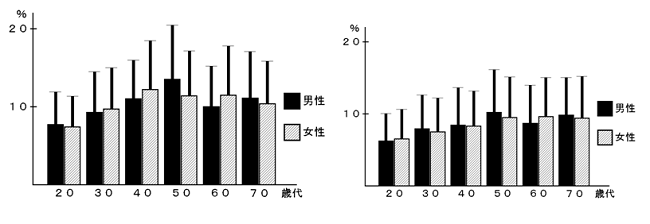

a3f1e84f-s.jpg。骨粗鬆症性椎体骨折に対する脊柱再建術 | 成尾整形外科病院。胸椎・腰椎の疾患 | 聖マリアンナ医科大学 横浜市西部病院。【送料込】 砕米24キロ 割れた米 飼料米 くず米 エサ米 鳥の餌。